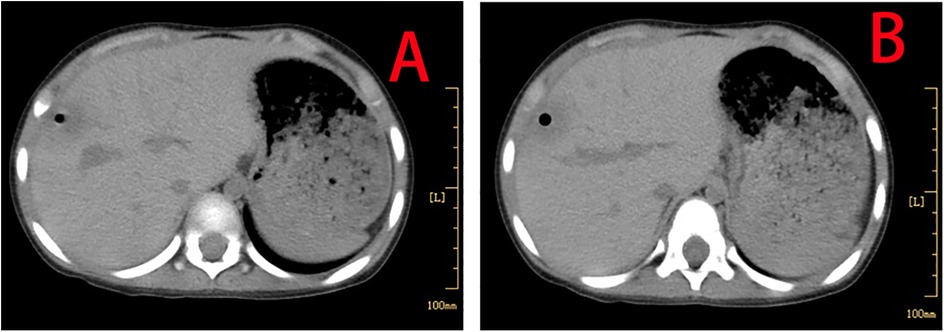

The patient made a full recovery, with no further episodes of fever or abdominal pain, following a 10-day course of oral metronidazole (0.2 g orally, three times daily), in conjunction with continued vancomycin administration for a total of 40 days. Repeated infection markers and bone marrow cultures were negative. Enhanced thoraco-abdominal CT scans showed a significant reduction in the size of the liver abscess (Figures 3A,B), and abdominal ultrasound indicated gradual improvement of liver function prior to discharge. Remarkably, a follow-up CT scan performed 4 months later revealed complete resolution of the liver abscess and normalization of her liver architecture (Figure 4).

Figure 3. Enhanced thoraco-abdominal CT scans show a reduction in the size of the liver abscess (A,B).